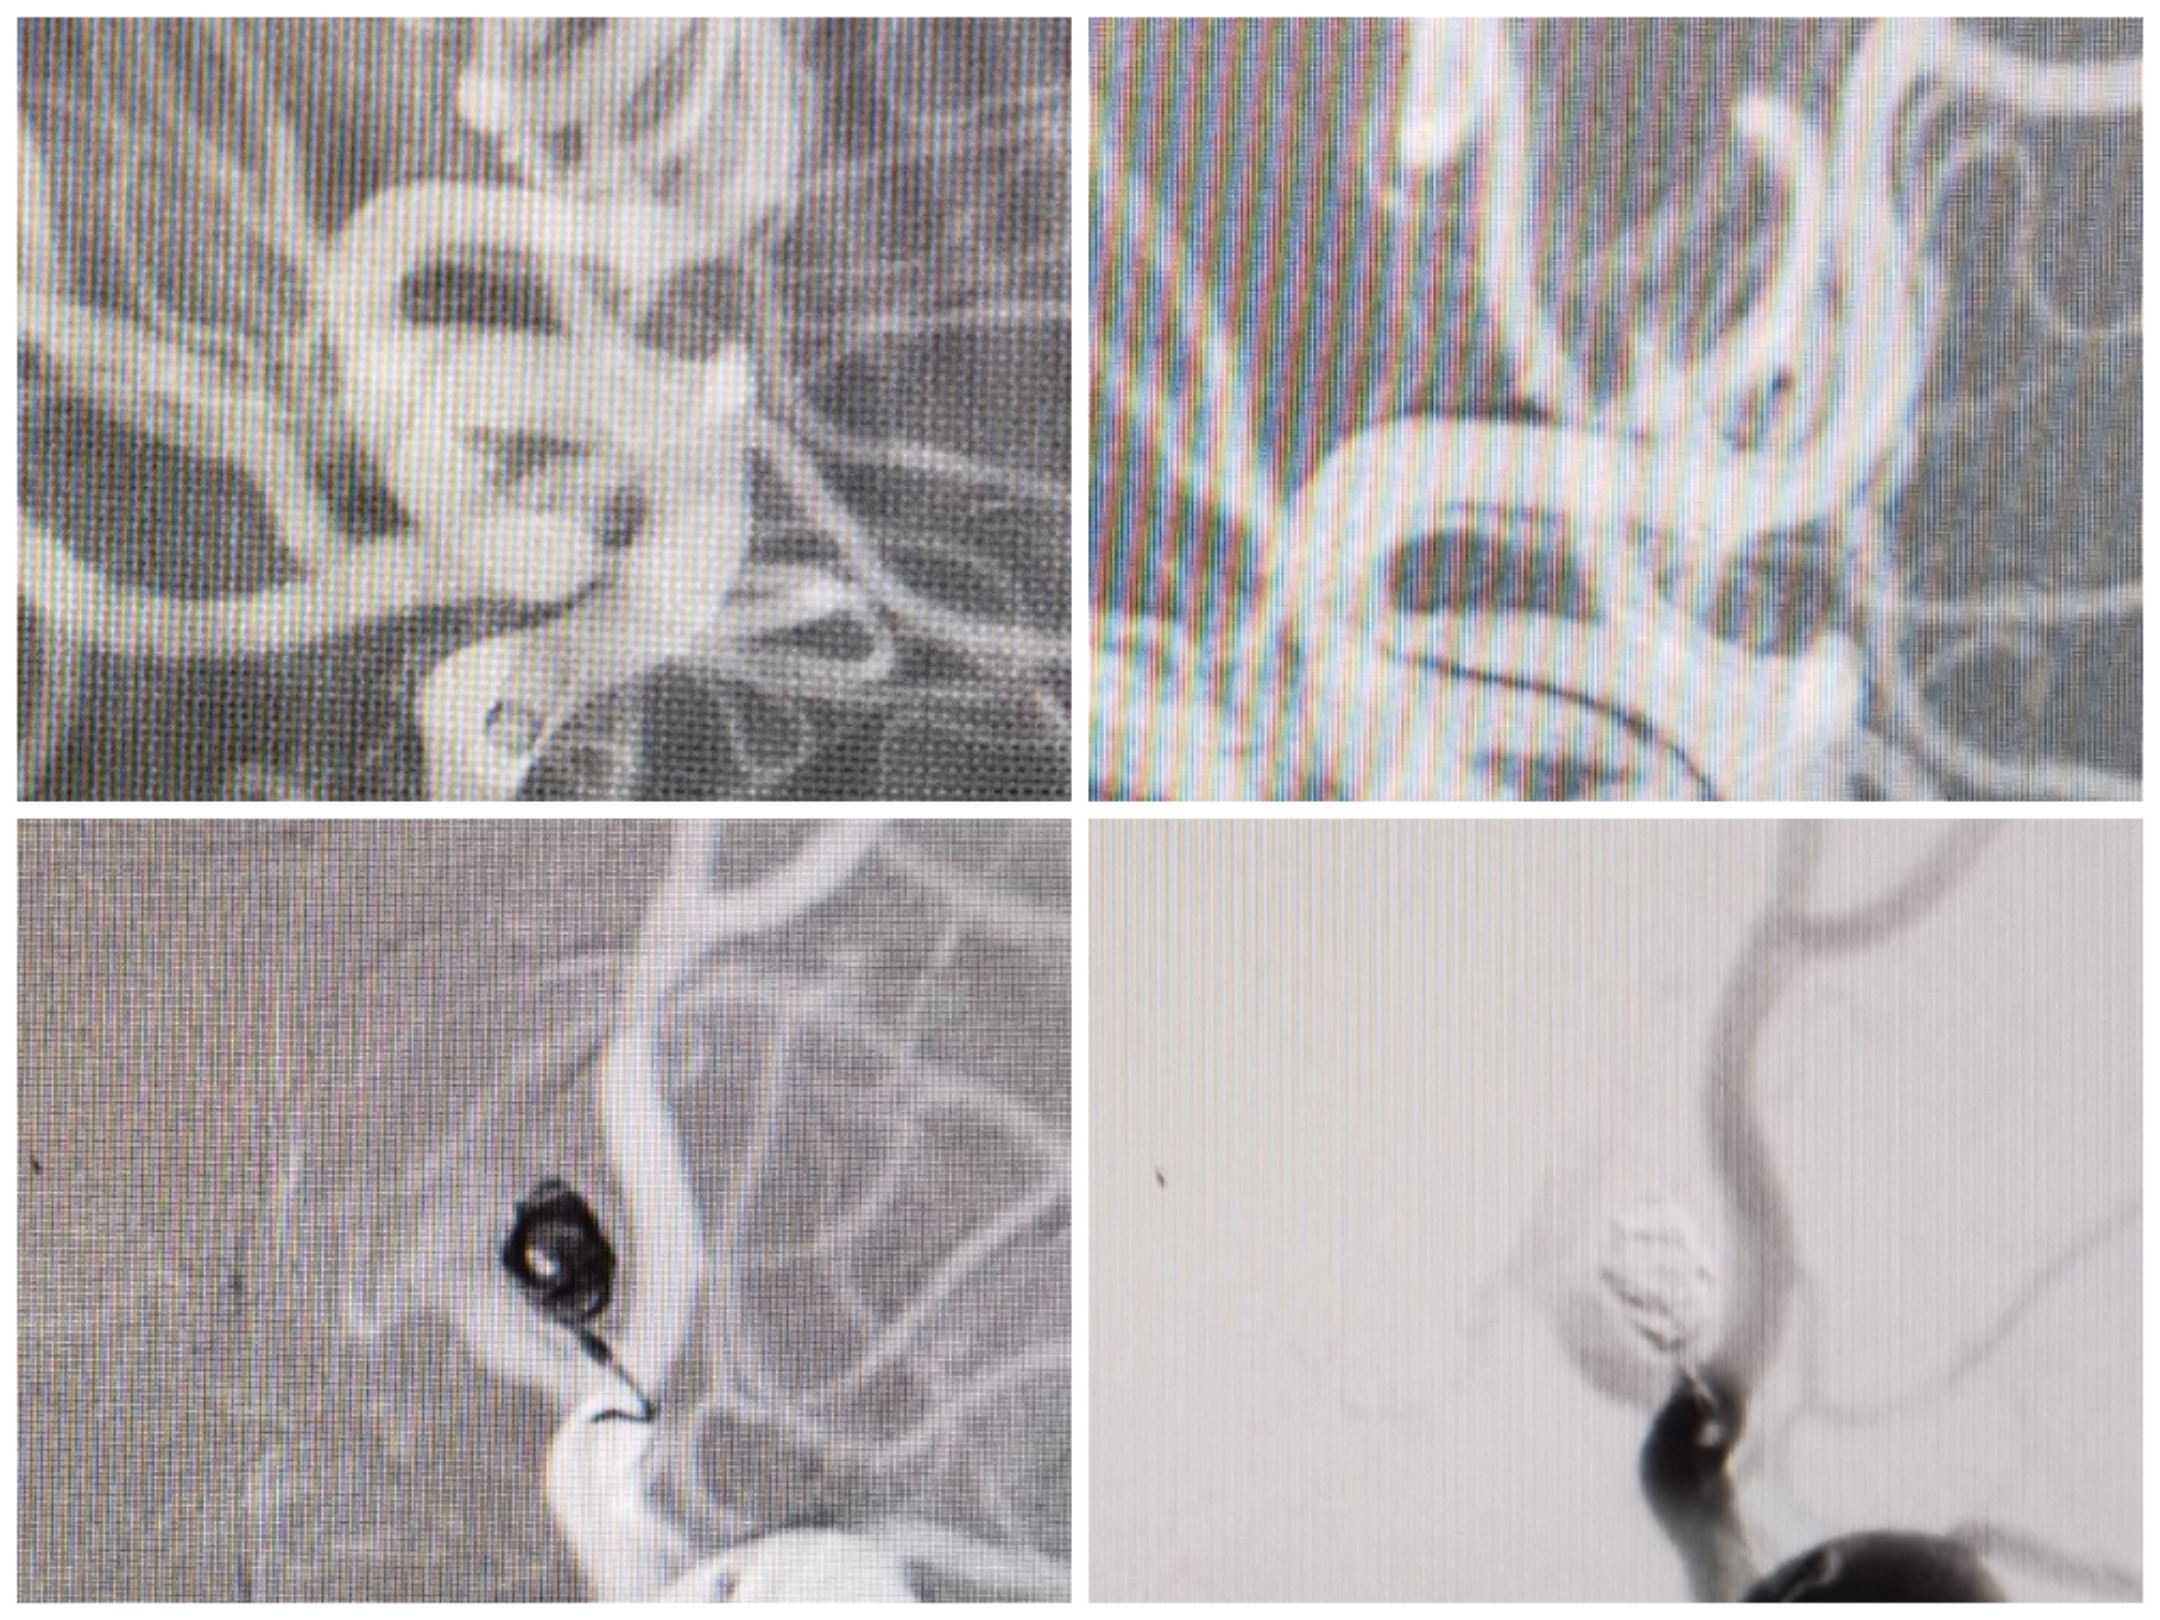

栓塞过程:塑了S型指向微管。

术后情况:前交通动脉瘤栓塞术后。双侧大脑前动脉显影良好